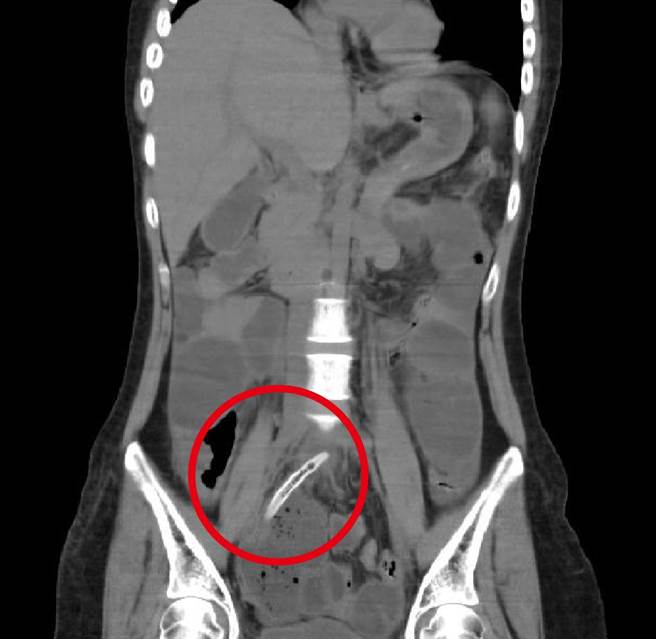

经电脑断层检查后发现,在迴肠与结肠交界的部位有4公分的牙籤造成肠穿孔与脓疡。(台中医院提供/张妍溱台中传真)

台中市38岁陈女士4月份因腹痛、发烧到医院求诊,经电脑断层检查后发现,在迴肠与结肠交界的部位有4公分牙籤造成肠穿孔与脓疡,经由消化外科医师徐玮呈採「腹腔镜微创手术」取出牙籤,症状获缓解,陈女告诉医师,因不小心误食固定爌肉上牙籤,直到疼痛变本加厉又发烧赶紧就医,险致命。

台中医院消化外科医师徐玮呈表示,当时陈姓女患者的腹部牙籤已穿刺肠壁,肠壁已发炎形成脓痬,进而引发感染到皮下组织而开始发烧,赶紧安排「腹腔镜微创手术」,取出牙籤及肠道修补,再进行伤口清创及脓疡引流;所幸及时就医处置,若穿刺其他重要器官恐大出血致命,相当危险。